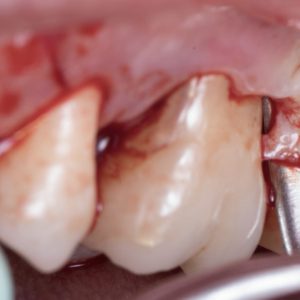

Hard tissue management: osteotomy, apicoectomy, root-end cavity preparation and filling.

Piezoelectric microsurgery.

Highlights from past editions